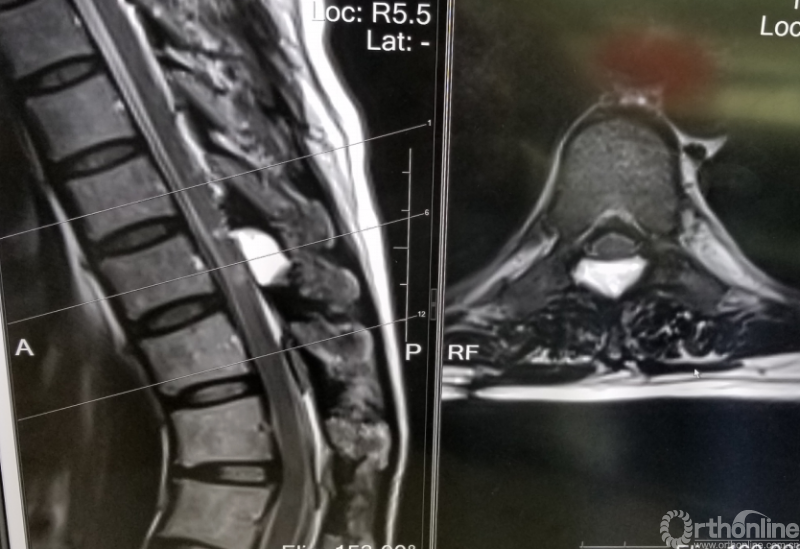

脊柱内镜手术通常作为首选手术方法,能有效地减压并进行相应的处理。适用于胸椎管狭窄症,如胸椎黄韧带肥厚症、胸椎间盘突出症、胸椎后纵韧带骨化症等,尤其适合单节段狭窄者。

2.胸椎椎管内囊肿:在脊柱内镜下进行病病灶切除术等;